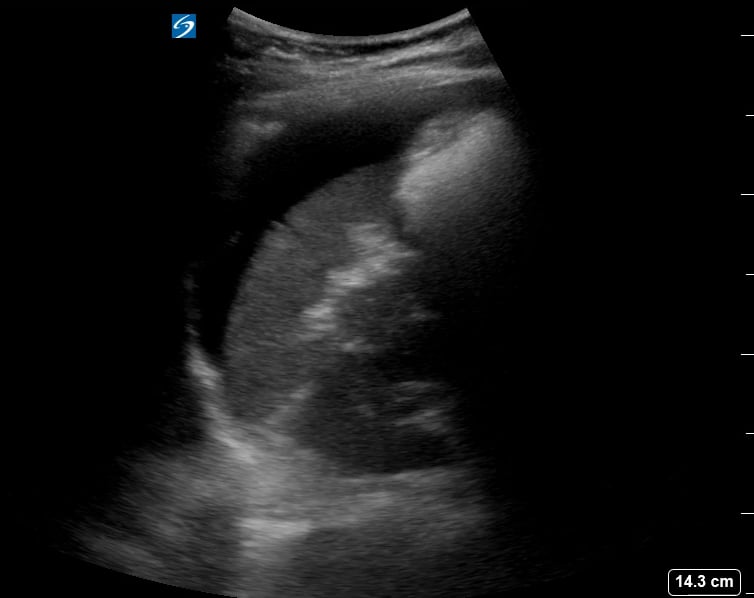

Ultrasound is the primary diagnostic tool for ectopic pregnancies, allowing visualization of the gestational sac outside the uterine cavity. Medical professionals rely on sonographic findings, alongside clinical symptoms and hCG levels, to confirm the diagnosis and guide appropriate management, including medication or surgery.